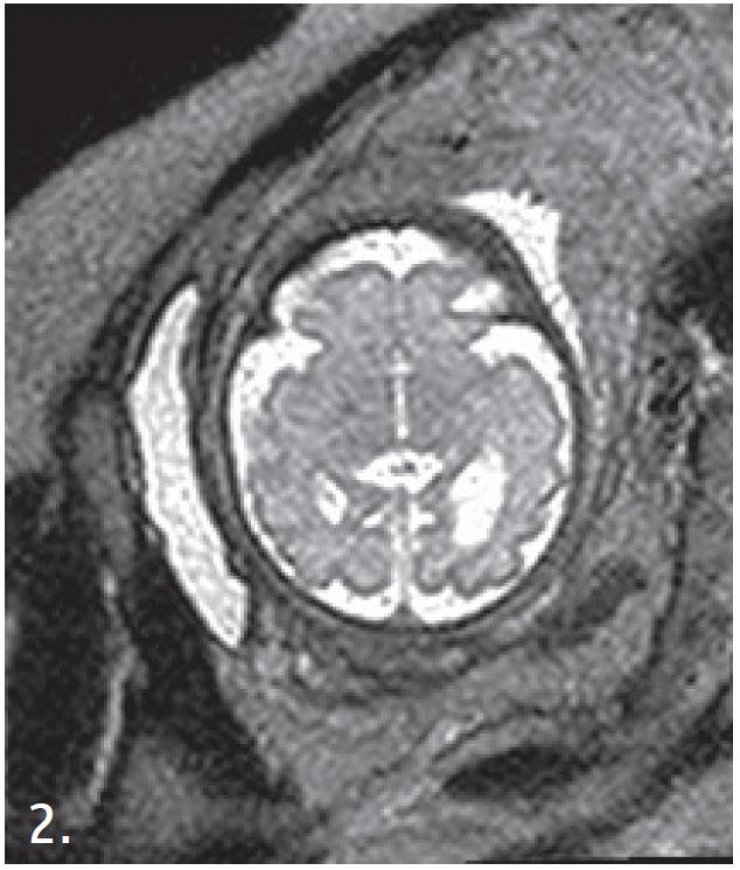

Γιατροί στο Κέντρο Μελέτης Εγκεφάλου στο Kings College του Λονδίνου δουλεύουν πάνω στην τεχνική της μαγνητικής τομογραφίας για τη χαρτογράφηση των εγκεφάλων των εμβρύων, που βρίσκονται ακόμη στη μήτρα.

Οι παραδοσιακοί τομογράφοι δουλεύουν παίρνοντας μια σειρά φωτογραφιών του σώματος, που με τη βοήθεια λογισμικού στη συνέχεια μετατρέπονται σε τρισδιάστατες απεικονίσεις. Οι ασθενείς πρέπει να μένουν όσο μπορούν πιο ακίνητοι, ώστε η τομογραφία να είναι όσο πιο ακριβής γίνεται.

Αυτό όμως δεν μπορεί να συμβεί στην περίπτωση των εμβρύων, που κινούνται μέσα στον αμνιακό σάκο. Η μόνη τεχνική απεικόνισης που είχαμε μέχρι σήμερα αφορούσε τεχνικές μίας λήψης και στη συνέχεια παγώματος της εικόνας. Τώρα, ένα ειδικό λογισμικό επιτρέπει να κάνουμε απεικονίσεις, ακόμη κι όταν υπάρχει κίνηση. Και αυτό είναι ένα μεγάλο βήμα. Μας επιτρέπει να δούμε πώς αναπτύσσονται οι συνδέσεις των νευρώνων του εμβρύου, όσο αυτό βρίσκεται ακόμη μέσα στη μήτρα. Ο χάρτης του εγκεφάλου που δημιουργούν με αυτόν τον τρόπο οι επιστήμονες ονομάζεται Connectome.

«Απεικονίσαμε τον τρόπο που το νερό κινείται στον εγκέφαλο. Το νερό κινεί προς τα πάνω ή προς τα κάτω τις νευρικές ίνες. Βλέπουμε την κίνηση και συμπεραίνουμε που βρίσκονται οι νευρώνες. Άρα μπορούμε να ελέγξουμε τη λειτουργία τους. Να δούμε πώς αλλάζει η ροή του αίματος στον εγκέφαλο. Όταν ο εγκέφαλος ενεργοποιεί μια συγκεκριμένη περιοχή, χρειάζεται περισσότερο αίμα. Μπορούμε να το δούμε. Μπορούμε λοιπόν να συμπεράνουμε από τις αλλαγές στη ροή του αίματος ποια μέρη του εγκεφάλου είναι ενεργά και ποια μέρη συνεργάζονται. Άρα βλέπουμε τη λειτουργία του εγκεφάλου με αυτή την μέθοδο» εξήγησε ο Ντέιβιντ Έντουαρντς.